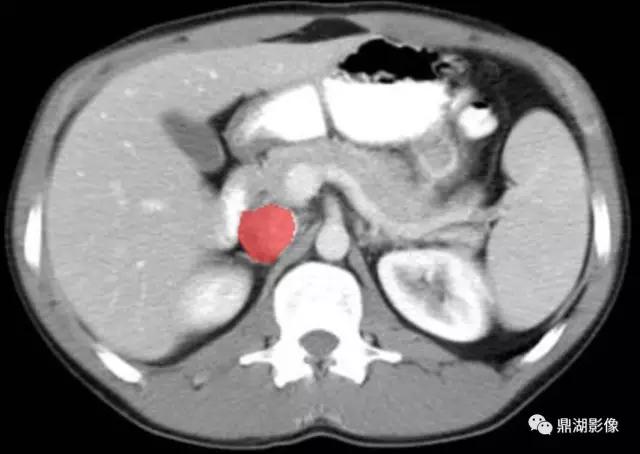

脾静脉(Splenic Vein)

肠系膜上静脉(Superior Mesenteric Vein)

肠系膜上动脉(Superior Mesenteric Artery)